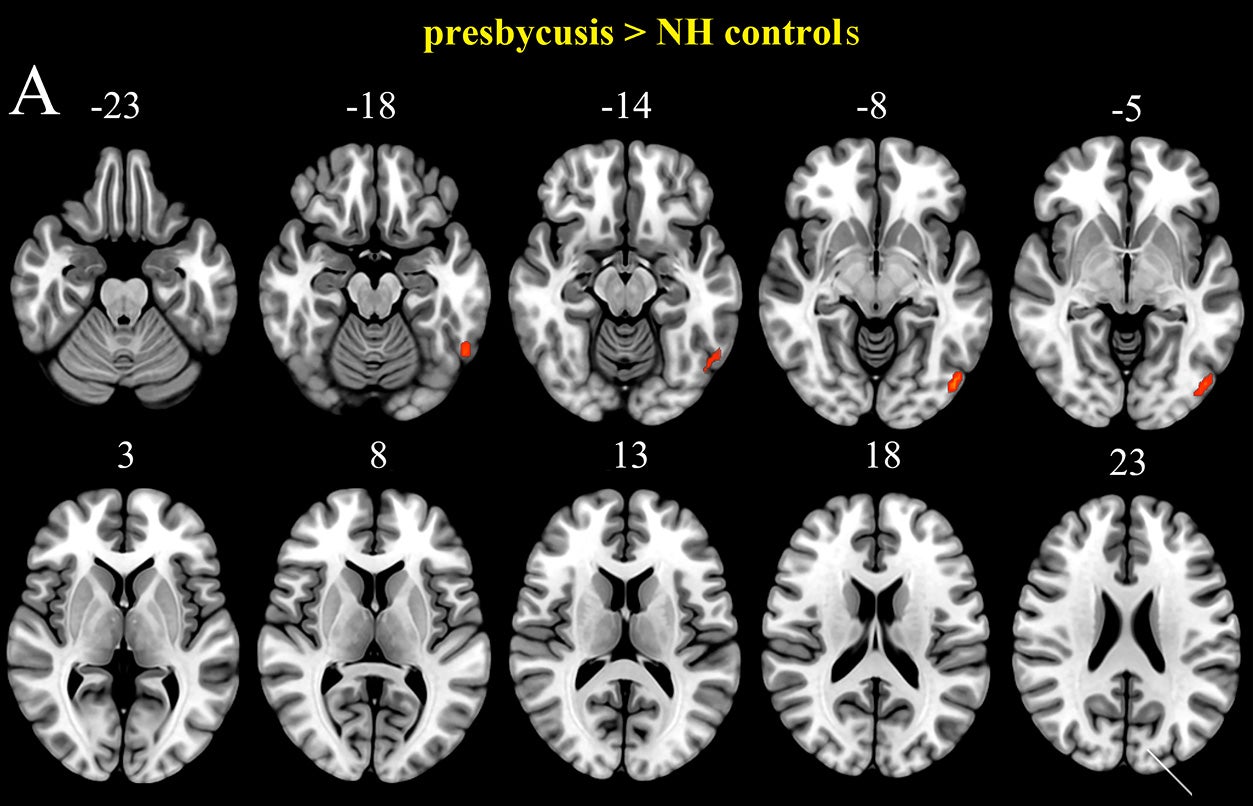

Methodological observations regarding GMV reductions observed in association with presbycusis across multiple brain regions were confirmed using anatomical comparison with those who had normal hearing. Included in these areas were the bilateral superior temporal gyrus and superior temporal pole, middle cingulate cortex, insula, Heschl’s gyrus, fusiform gyrus, and supplementary motor area. The right middle temporal gyrus, hippocampus, calcarine, precuneus, left putamen, medial superior frontal gyrus, and inferior parietal lobule also showed reductions in the presbycusis group compared to controls.

While some areas showed a reduction of ALFF for presbycusis relative to controls, the right inferior temporal gyrus, left calcarine, and inferior occipital gyrus all exhibited increased ALFF.